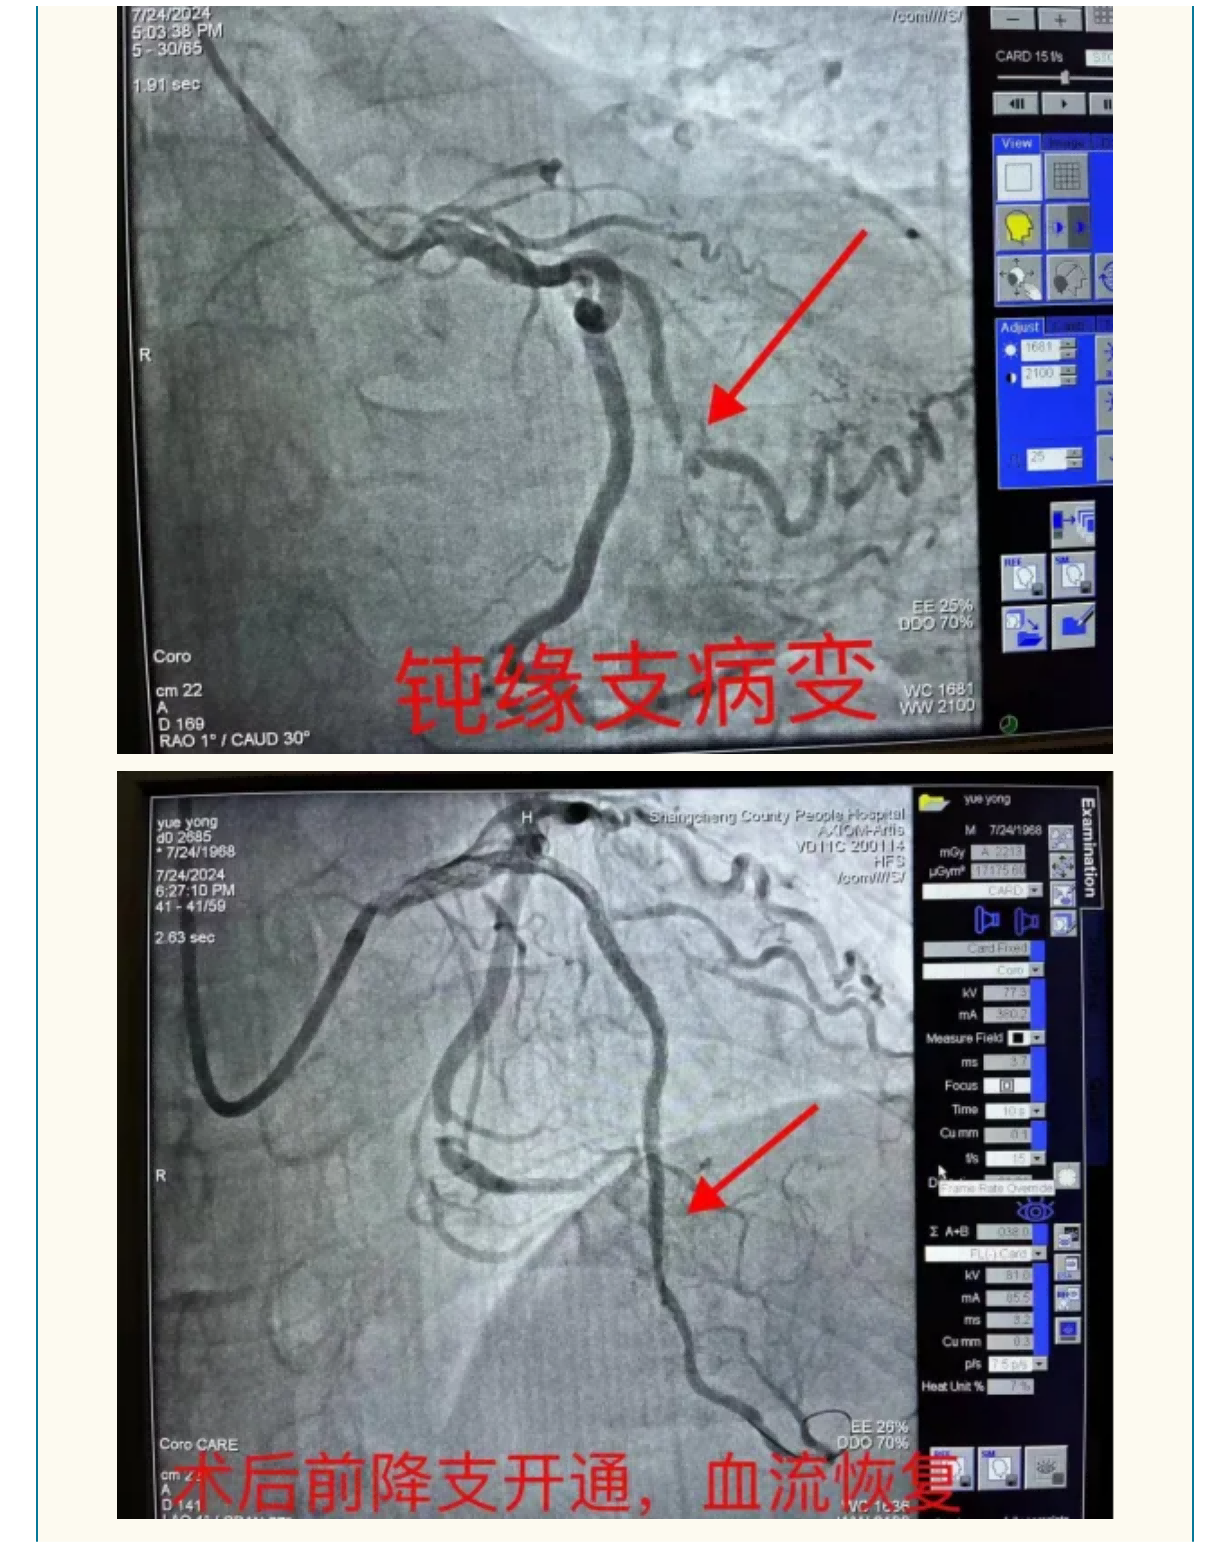

勇攀“心”高峰:我院心血管内科成功救治重症冠心病患者